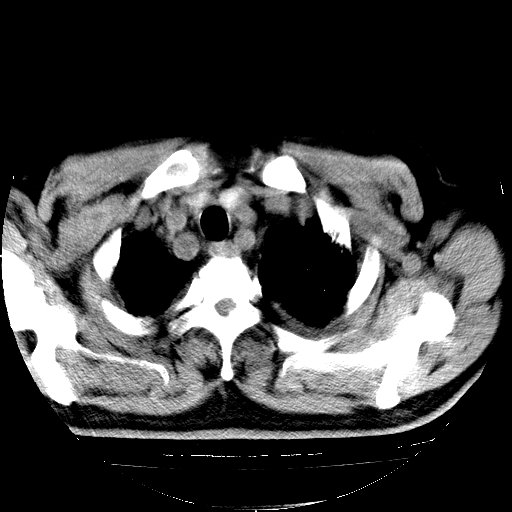

男,68岁,咳嗽、胸闷、发烧三天,查体:双肺散在湿罗音。

4.肺原性心脏病;

5.双侧胸腔少量积液;双侧胸膜增厚。

慢性支气管炎伴感染、肺气肿;间质性病变;双侧胸腔积液。